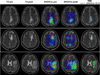

Experimental design: We report a prospective longitudinal imaging study performed in 25 IDH-mutant glioma patients receiving adjuvant radiation and chemotherapy. A newly developed 3D MRS imaging was used to noninvasively image 2HG. Paired Student t test was used to compare pre- and posttreatment tumor 2HG values. Test-retest measurements were performed to determine the threshold for 2HG functional spectroscopic maps (fSM). Univariate and multivariate regression were performed to correlate 2HG changes with Karnofsky performance score (KPS).

Results: We found that mean 2HG (2HG/Cre) levels decreased significantly (median = 48.1%; 95% confidence interval = 27.3%-56.5%;P= 0.007) in the posttreatment scan. The volume of decreased 2HG correlates (R(2)= 0.88,P= 0.002) with clinical status evaluated by KPS.

Conclusions: We demonstrate that dynamic measurements of 2HG are feasible by 3D fSM, and the decrease of 2HG levels can monitor treatment response in patients with IDH-mutant gliomas. Our results indicate that quantitative in vivo 2HG imaging may be used for precision medicine and early response assessment in clinical trials of therapies targeting IDH-mutant gliomas.